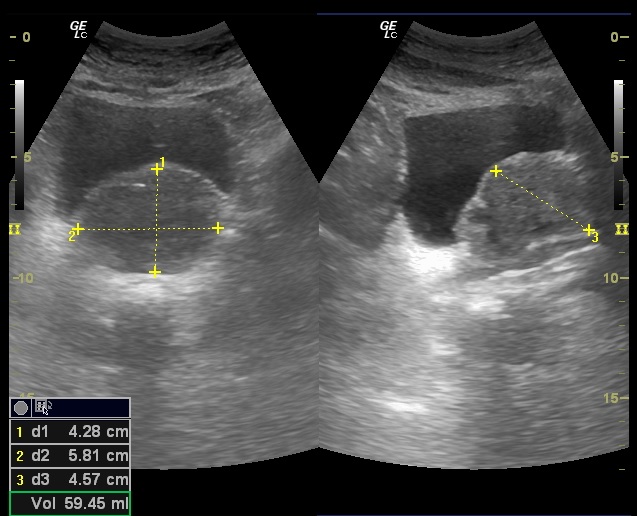

Glándula prostática de 4,28 x 5,81 x 4,57 cm (Figura 1). Volumen prostático: 59,45 ml. Pared de vejiga no engrosada. Se objetiva divertículo vesical (Figura 2) único localizado en pared postero lateral. No se observan lesiones intravesicales ni tampoco en la luz del divertículo (Figura 3). Volumen posmiccional 240 cc.